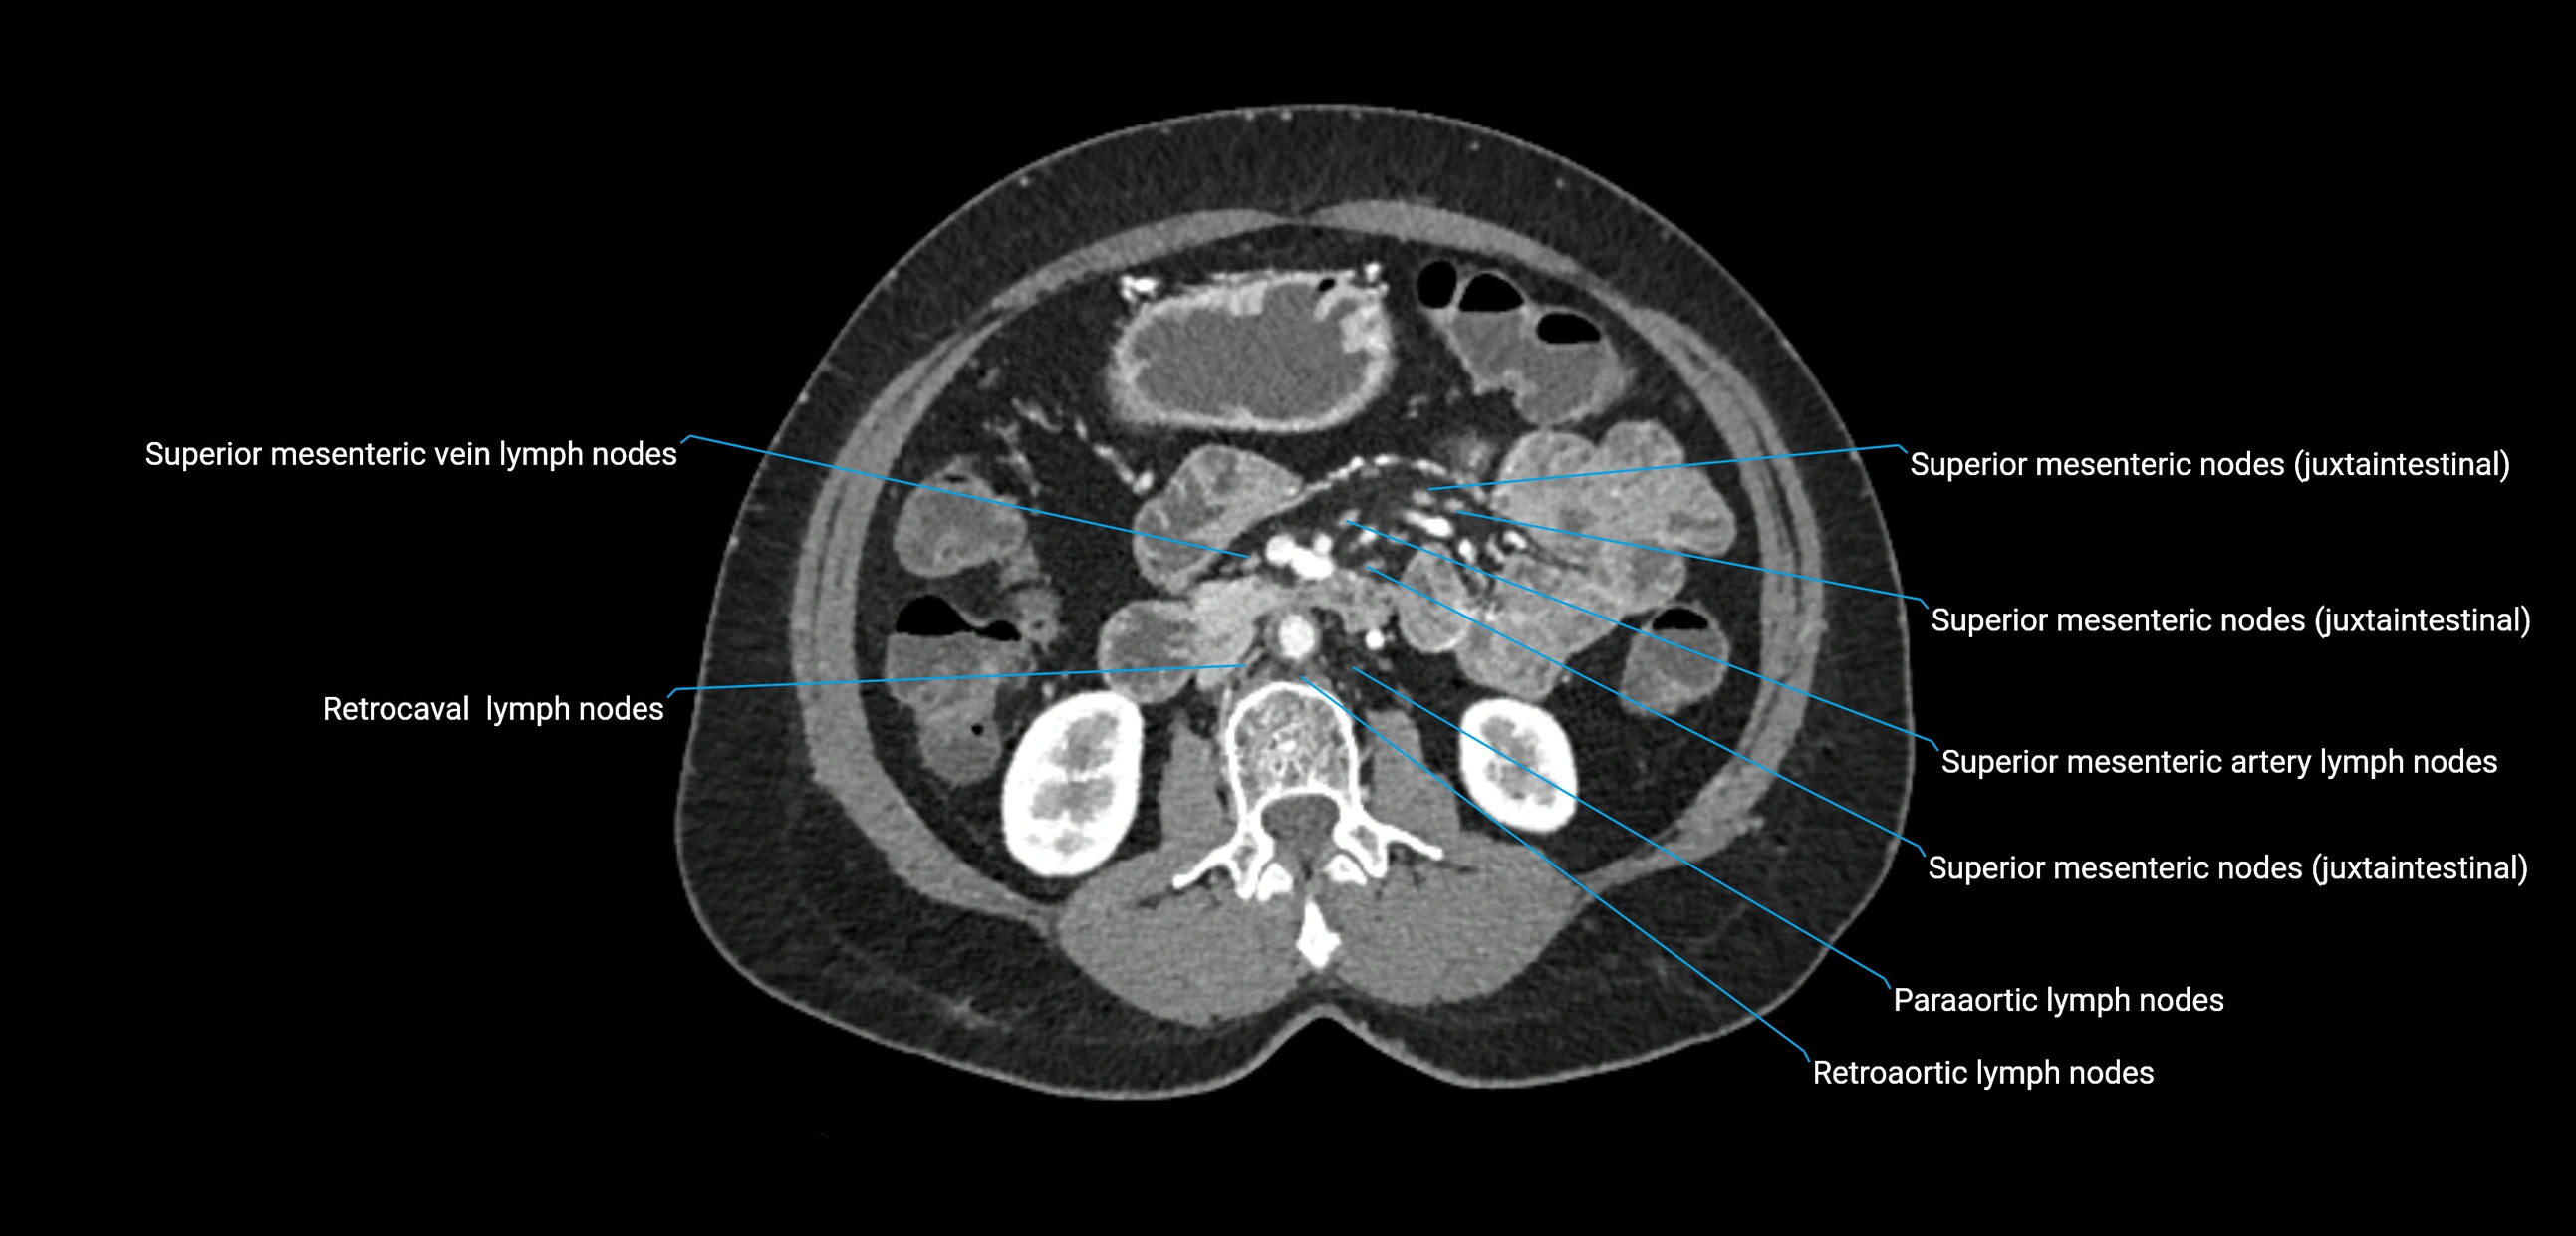

CT Appearance

CT Pre-Contrast:

• Nodes appear as soft-tissue density nodules adjacent to the aorta and IVC

CT Post-Contrast:

• Normal nodes enhance homogeneously

• Malignant nodes may show heterogeneous enhancement, central necrosis, or conglomerate formation

• Size >1 cm short axis is suspicious, though morphology and distribution are equally important

CT image

image